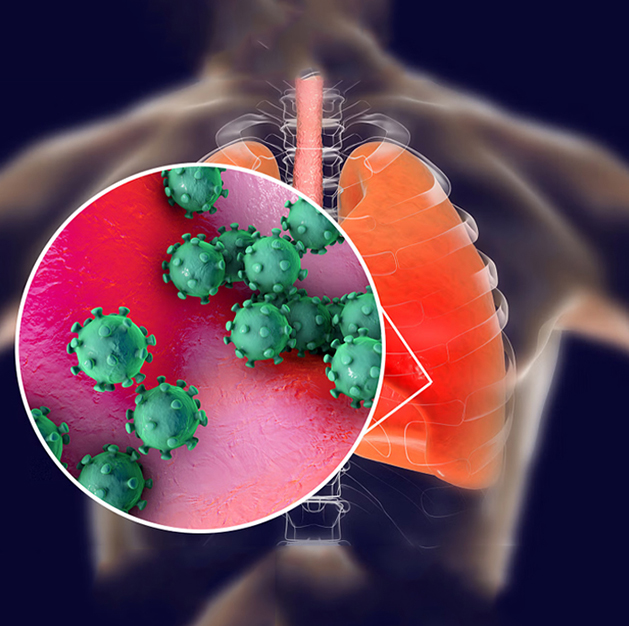

Respiratory Infections & ARDS